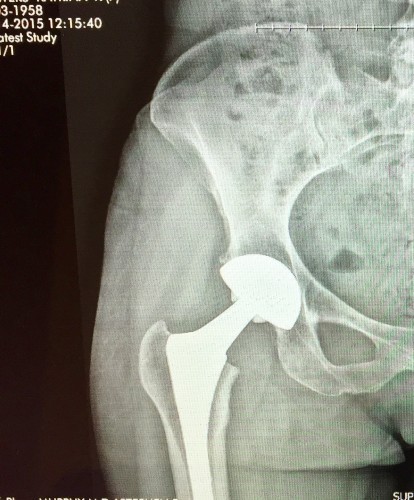

The moment my orthopedist flipped the switch on the light box and brought up the ghostly X-ray images of my two arthritic hips was the first time it hit me: I’m not indestructible after all. In fact, I’m not even in charge here. I’d done everything “right” — exercised regularly, eaten well, practiced yoga for years, bought well-cushioned new sneakers every spring. I was pretty sure all that good living was buying me both time and health.

And yet, the pain I’d been believed for months to be a groin pull was suddenly revealed to be something else entirely. And with that my illusions were shattered.

“Looks like you’ll be needing a couple of hip replacements,” the doctor said, pointing first to the bone spur that was not a groin pull at all – it looked like a shark’s tooth, sharp and vicious; no wonder I was gasping every time I moved my leg to the side — and then to the deterioration in the joints. “Bone on bone here,” he said, tracing the fuzzy line at the head of my left femur. “And clearly degenerating over here as well,” he said, pointing to the other side.

And so, standing there staring at the first of what would be many x-rays, I got a little wiser. I learned what advanced osteoarthritis looks like. And I realized I’m not in control of the way my body is succumbing to the realities of wear and tear, age, and mortality.